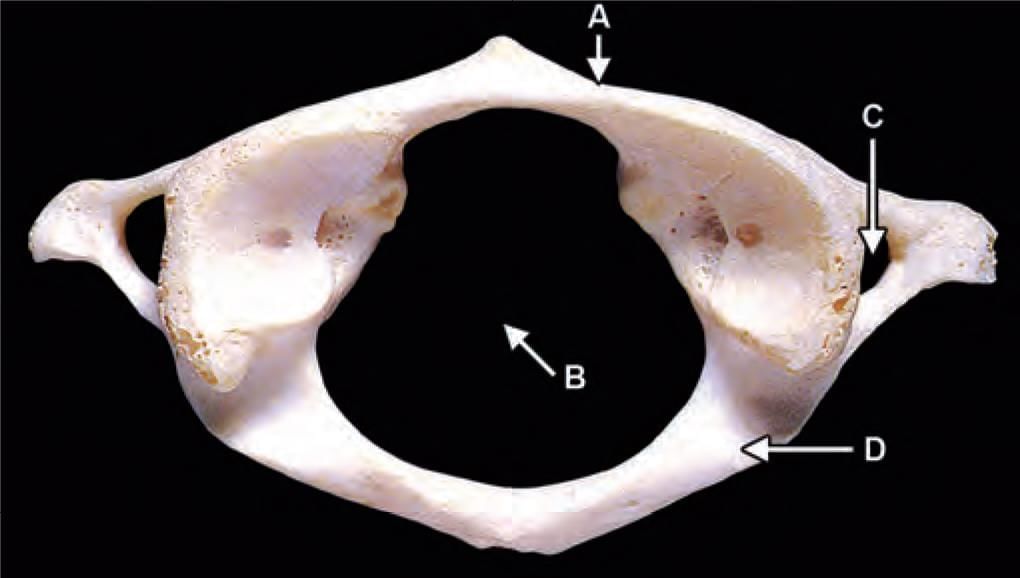

Third part of vertebral artery is related to which of the following marked region in the following diagram? (INI-CET Nov 2021)